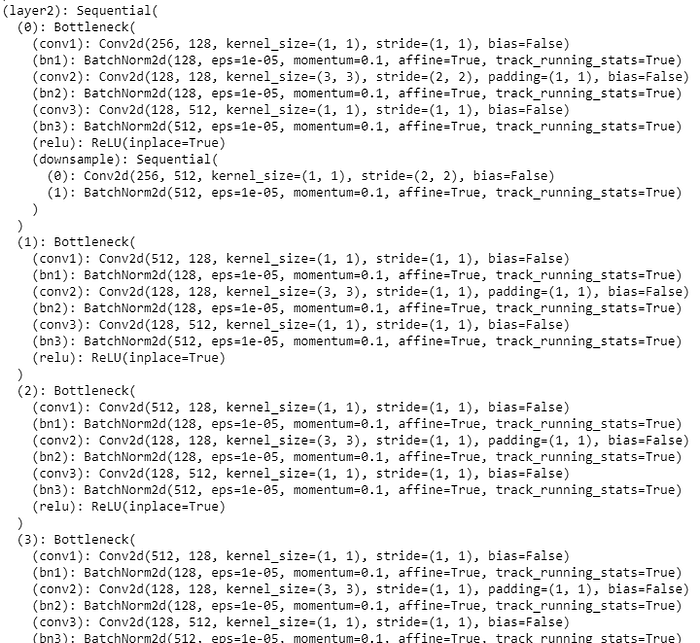

We used ResNet-50 convulational neural network (CNN) in this experiment for deep learning for image recognition and classification. The model layers are as shown below. We used optimizer= ‘Adam’.